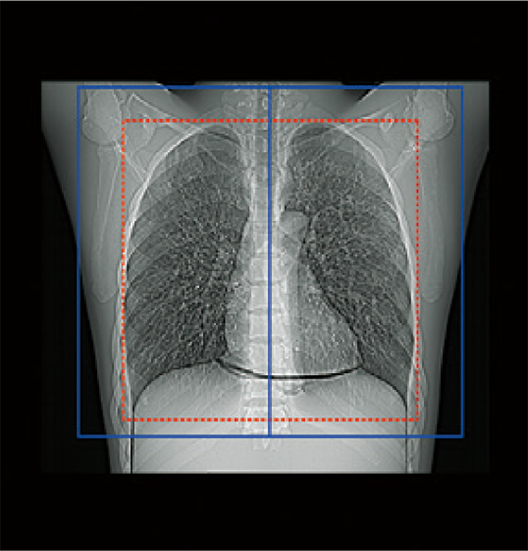

透過掃描定位圖影像,即可自動設定掃描範圍,有助於提升掃描位置的再現性與檢查效率,進而縮短整體檢查時間。

掃描範圍的邊界可依各醫療機構的作業習慣預先設定,實現符合需求的自訂化操作。操作者亦可隨時檢視與調整自動計算出的掃描範圍。*4

Chest

紅色:自動設定位置

藍色:自動設定位置 + 設定邊界